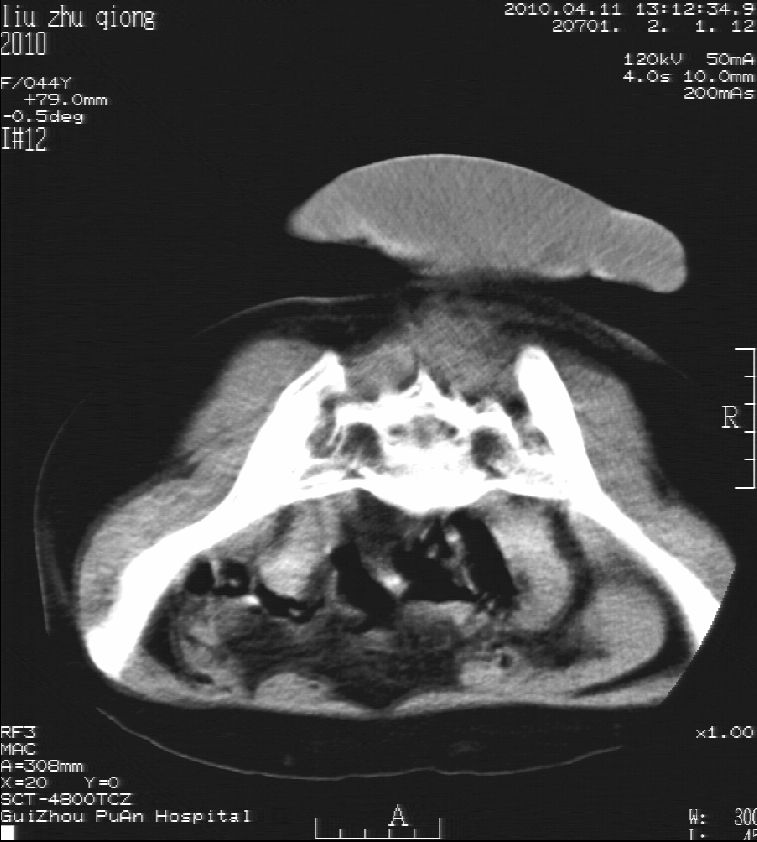

刘某,女,44岁,生第一胎时发现腰背部肿块,黄豆大小,至今17年,呈逐年增大,现行ct检查如下,敬请各位指点。

病史:女,44岁,腰背部肿块,黄豆大小,17年,呈逐年增大。

ct示:骶骨见软组织密度影,似见细条状,或花边状高密度影,考虑不典型钙化灶,向后生长,超出皮肤,可见骶骨破坏,第5幅ct图似与骶管相通。

诊断:脊索瘤

病程长,生长慢,肿块巨大,考虑神经纤维瘤,脂肪密度可以用肿瘤生长过程中包裹入皮下脂肪解释。